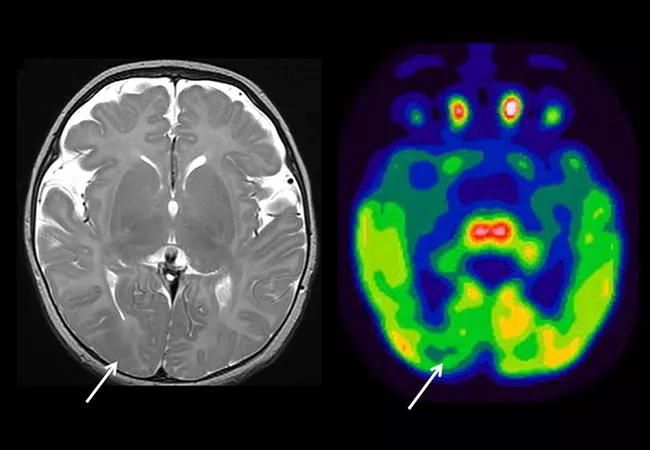

Image at top shows T2-weighted MRI and FDG-PET images from a 3-month-old infant with epileptic spasms and focal seizures. Arrows indicate focal areas of hypointensity and hypometabolism consistent with focal cortical dysplasia.